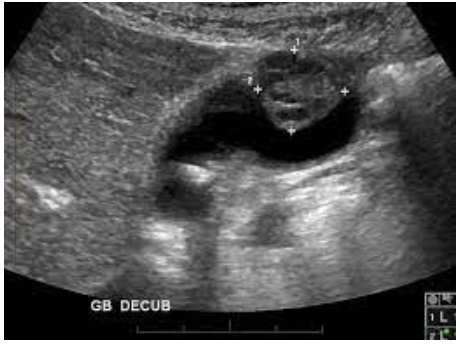

What pathology is in the image below

Sludge - Low level interal echoes, without shadows, no wall/ border